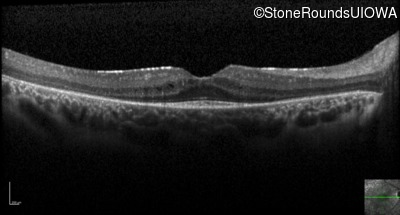

Optical Coherence Tomography - Right - 20/40 -2

Exemplar / OCT Stack